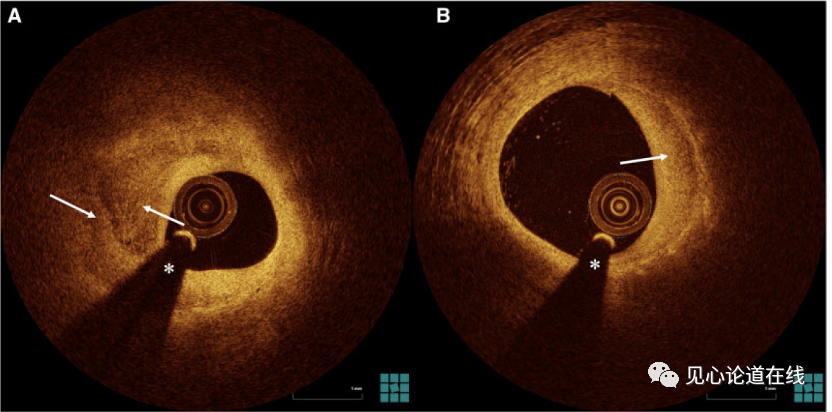

本研究从麻省总医院OCT注册研究及EROSION研究数据库中筛选出349名ACS患者,使用冠脉造影图像研究非罪犯病变的发生率,其中有229名患者使用光学相干断层显像(OCT)分析非罪犯病变的影像特征。其中,非罪犯斑块定义为:定量冠脉造影(QCA)直径狭窄≥30%的斑块。分层斑块在OCT图像上定义为:在≥3个连续图像上可见、存在1层及以上具有不同光学密度的分层、并与其下方结构有明显分界的斑块(见图1)。

图1. 分层斑块的OCT图像(箭头所示为不同光学密度的分层)